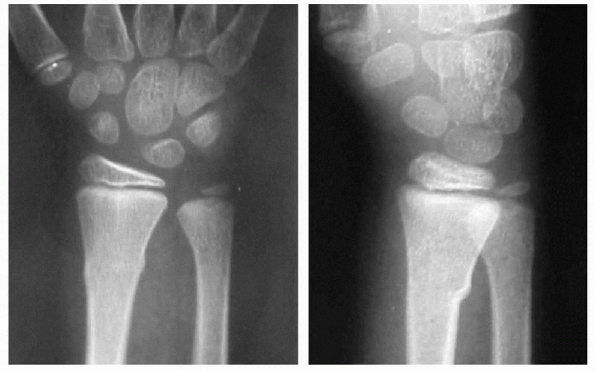

skeletal injuries in the pediatric population. The mechanism is usually

forearm. The distal one-third radius is usually the most common site of

injury. Although most metaphyseal forearm fractures can be

conservatively treated without sequelae in skeletally immature patients

due to remodeling, some fractures at the midshaft and proximal

Distal metaphyseal and epiphyseal

fractures occur in the older child (most commonly in boys between 13

and 15 years, and girls between 12 and 13 years). This difference

reflects the difference in the average age of skeletal maturation

between the two genders. Near skeletal maturity, the amount of cortical

bone at the diaphysis

P.126increases and the metaphyseal area decreases, making the distal radius the weaker portion of forearm bone.